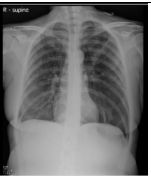

1.

7.CC: cough for one year and back pain